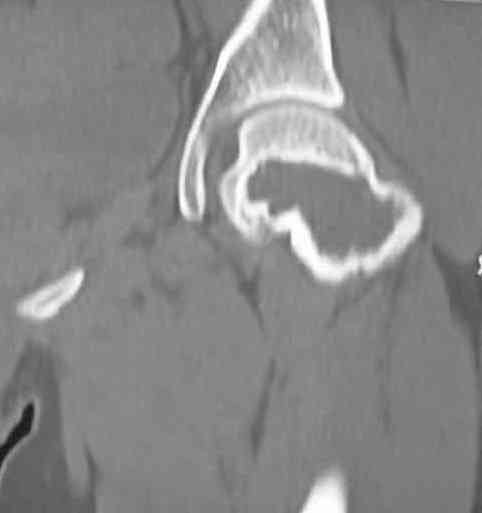

Больная Л.,   23 года.

Из анамнеза:со слов больной в 2006 г. появились боли правой н/конечности, обратилась поместу жительства к хирургу, было выполнена МРТ поясничного отдела позвоночника,назначено физиолечение. Через 2 месяца боли прекратились, через 4 месяца рецидивболевого синдрома. С 2006 – 2010 проводилось консервативное лечение по поводуостеохондроза поясничного отдела позвоночника. В октябре 2010 г. боли усилились.Выполнены Ro и КТправого тазобедренного сустава, выявлен очаг патологической перестройки. Быланаправлена на консультацию в УНИИТО.

В УНИИТО виюне 2011 г. поставлен дифференциальный диагноз между фибромой, солитарной костнойкистой и гигантоклеточной опухолью.